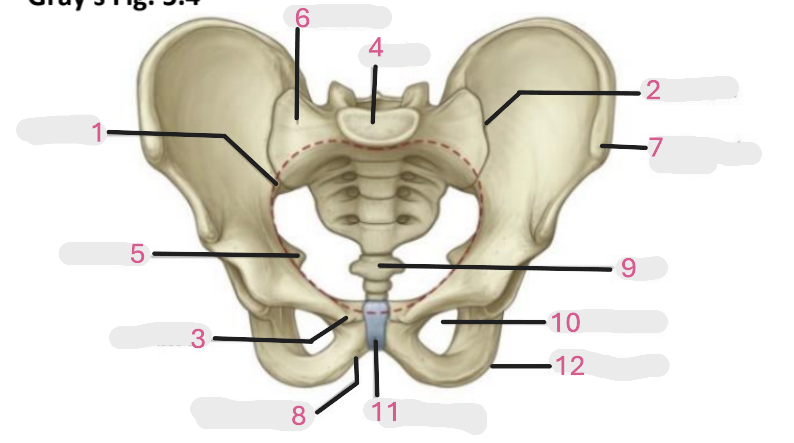

Where is the pelvic inlet

1

Where is the sacro-iliac joint

2

Where is the pubic tubercle

3

Where are the S1 body

4

Where is the ischial spine

5

Where is the ala of sacrum

6

Where is the anterior superior iliac spine

7

Where is the ischiopubic ramus

8

Where is the coccyx

9

Where is the obturator foramen

10

Where is the pubic symphysis

11

Where is the ischial tuberosity

12